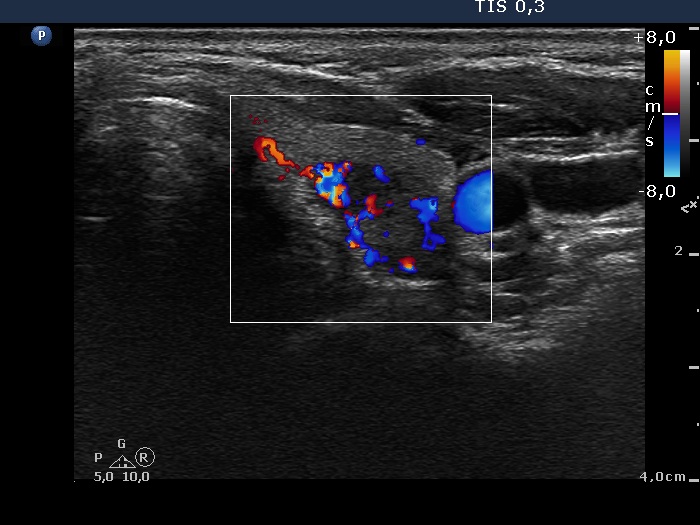

Right lobe, longitudinal scan

Left lobe, transverse scan, color Doppler mode. The lesion has increased intranodular blood flow.